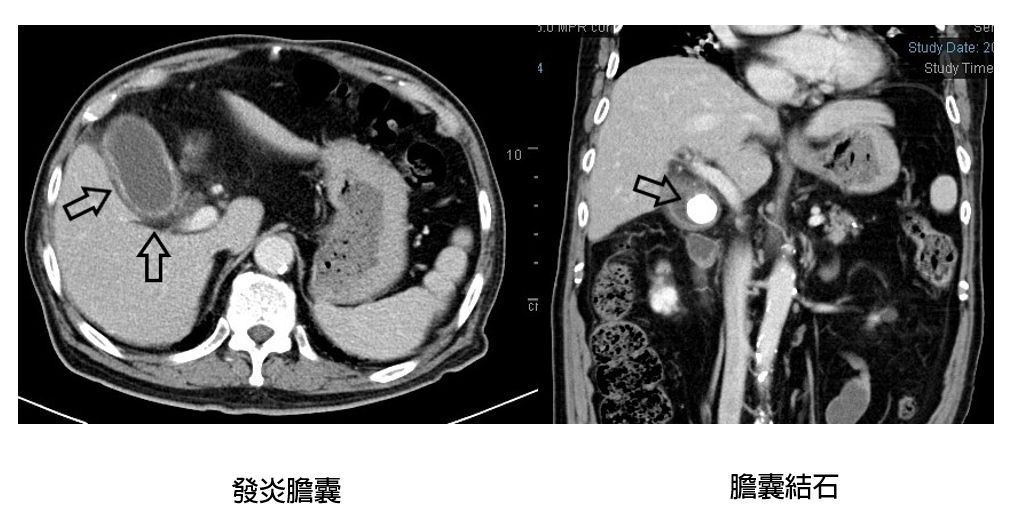

1名85歲男子有高血壓、糖尿病及慢性腎病的病史,上月因發燒及右上腹痛到亞東醫院急診就醫,經電腦斷層掃描後發現1顆3公分大且硬的膽結石及急性發炎。